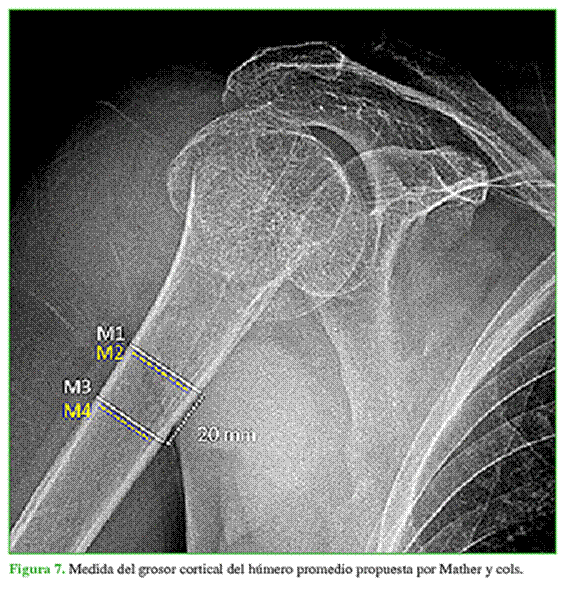

La evaluación radiográfica estuvo a cargo del mismo evaluador (N. N. A.), con las imágenes preoperatorias, junto con las del primero y último control posoperatorio, en la proyección anteroposterior de Grashey. En las radiografías preoperatorias, se evaluó el tipo de fractura según la clasificación de Resch, se obtuvo la medida del GCHP (Figura 7), cuyos resultados <6 mm se asocian con osteoporosis.

La medida consiste en la diferencia entre el grosor total de la diáfisis y el grosor del canal endomedular, medidos en dos niveles distintos: uno superior, cuando la diáfisis converge en dos líneas corticales paralelas, y otro 2 cm por debajo.3,13,16 Los controles radiográficos posoperatorios se realizaron inmediatamente luego de la cirugía y en la última consulta. Se midió la altura de la cabeza humeral (ACH) en relación con la placa, definida por la distancia entre una línea perpendicular al eje de la placa a nivel de su borde superior y otra línea paralela que pasa tangencialmente al extremo superior de la cabeza humeral, y el ángulo cervicodiafisario (ACD), formado por el eje diafisario del húmero y el eje perpendicular al cuello anatómico del húmero (Figura 8).7